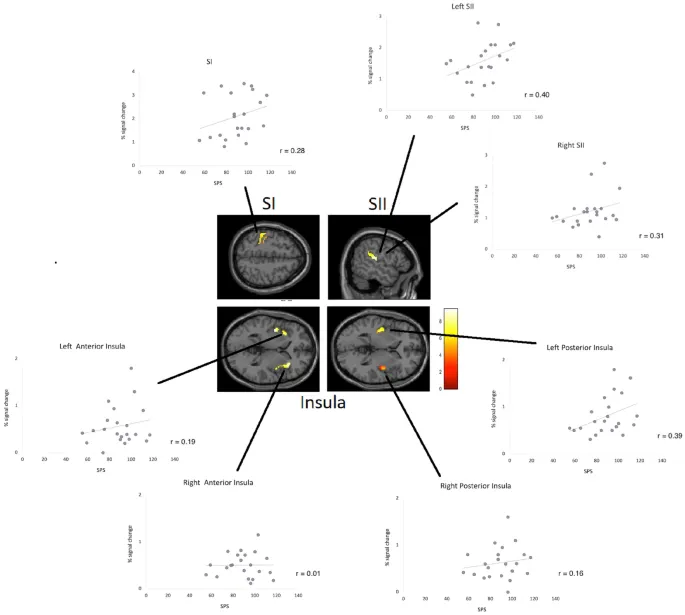

Рисунок 3 показывает диаграммы рассеяния взаимосвязей между СОЧ и областями мозга, связанными с соматосенсорной активностью (левая SI, SII, островок). Корреляции Пирсона демонстрируют тенденцию к положительной корреляции баллов СОЧ с активностью мозга для левой задней части островка (Пирсон, r = 0,39, p = 0,073; двустороннее). Правая задняя часть островка не показала корреляции с СОЧ. Кроме того, левая SII показала тенденцию к положительной связи с СОЧ (r = 0,40, p = 0,064). Другие области мозга, такие как SI, правая SII, правая задняя и билатеральная передняя части островка (а также DLPFC, ACC и медиальная PFC), не выявили значимых корреляций (или тенденций, все p > 0,10).

Чтобы проверить, сохраняется ли тенденция значимой корреляции между задней частью островка и СОЧ при контроле личностных черт, связанных с СОЧ (как показано выше), мы рассчитали частичные корреляции, используя нейротизм и открытость опыту, а также эмпатию (общий балл) в качестве контрольных переменных. Результаты подтвердили связь СОЧ с соматосенсорной активностью мозга в левой задней части островка (r = 0,48, p = 0,034). При контроле этих личностных черт корреляция с левой SII не показала значимого результата (r = 0,39, p = 0,090). Другие области мозга, рассчитанные с помощью частичных корреляций, остались незначимыми (все p > 0,10).

Учитывая, что эмпатия (и открытость опыту) могут считаться важными аспектами черты СОЧ, мы также провели частичные корреляционные анализы СОЧ с контролем только нейротизма. Результаты показали аналогичные результаты для связи СОЧ с соматосенсорной активностью мозга в левой задней части островка (r = 0,51, p = 0,018) и левой SII (r = 0,41, p = 0,065) (все остальные области p > 0,10).